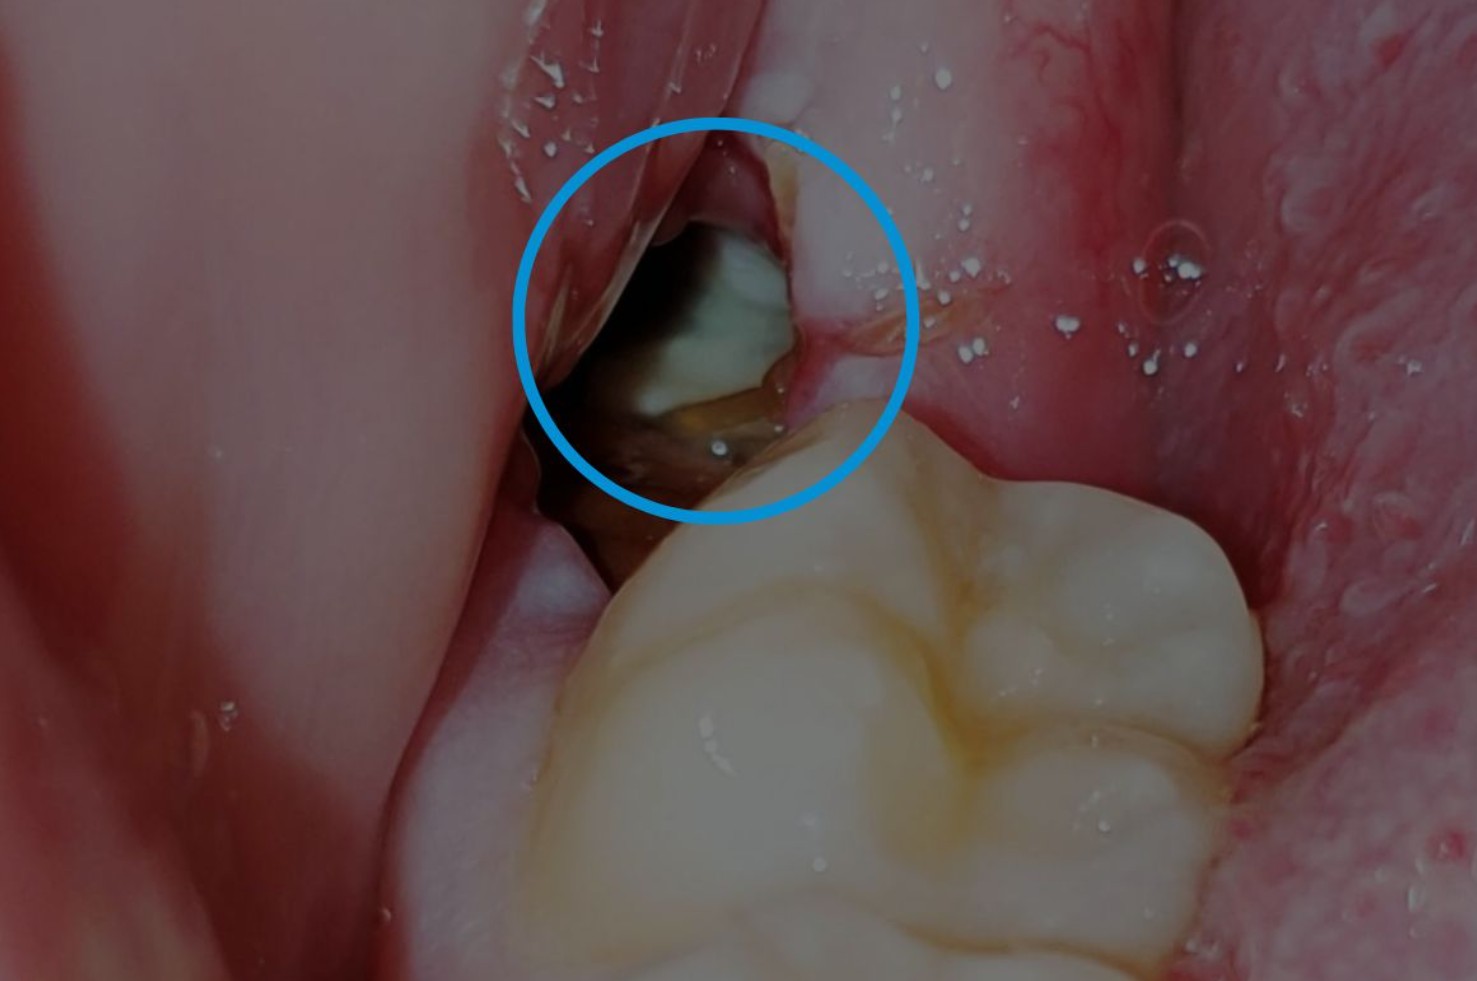

Tuy nhiên, khi răng khôn mọc lệch, mọc ngầm, hoặc gây viêm nướu tái phát, bác sĩ sẽ khuyến cáo nên nhổ sớm. Những trường hợp này không chỉ gây đau nhức mà còn có thể làm hư răng số 7 kế cận, hoặc tạo ổ nhiễm trùng kéo dài trong xương hàm.